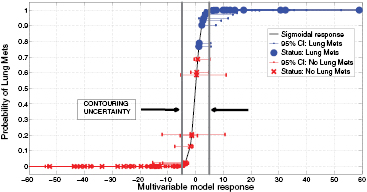

In order to evaluate the precision of the proposed model, we calculated how its response changes using texture features extracted from tumour contours that include surrounding edema. Supplementary appendix D.1 (stacks.iop.org/PMB/60/145471/mmedia) details the calculations. Overall, an absolute value of ± 4.89 was estimated as the uncertainty of the model due to contouring variations. This uncertainty is constant across all values of g(xi). Then, to summarize how the model can separate the instances of the two patient classes (LungMets versus NoLungMets), the vector  was computed for all patients using the multivariable model response of (7) and was transformed into the posterior probability π(xi) of observing outcome yi = 1 (i.e. developing lung metastases) given the input xi by using the logit transform of (2). Figure 7 displays the plot of π(xi) versus g(xi), along with the associated 95% confidence intervals (CIs) on g(xi) for i = 1, 2,..., N. For each bootstrap sample b used to calculate the final logistic regression coefficients of (7), a new value of

was computed for all patients using the multivariable model response of (7) and was transformed into the posterior probability π(xi) of observing outcome yi = 1 (i.e. developing lung metastases) given the input xi by using the logit transform of (2). Figure 7 displays the plot of π(xi) versus g(xi), along with the associated 95% confidence intervals (CIs) on g(xi) for i = 1, 2,..., N. For each bootstrap sample b used to calculate the final logistic regression coefficients of (7), a new value of  was calculated for i = 1, 2,..., N from the new coefficients computed on

was calculated for i = 1, 2,..., N from the new coefficients computed on  . Then, the lower and upper CI bounds were estimated for each point i by calculating the 2.5 and 97.5 percentiles from the bootstrap distribution of

. Then, the lower and upper CI bounds were estimated for each point i by calculating the 2.5 and 97.5 percentiles from the bootstrap distribution of  for b = 1, 2, ..., B. In figure 7, the dots represent patients who eventually developed lung metastases, and the crosses those who did not develop lung metastases. The uncertainty due to contouring variations around the classification threshold g(xi) = 0 is also shown, and supplementary appendix D.2 (stacks.iop.org/PMB/60/145471/mmedia) provides the detailed data (lung mets status, g(xi) and CIs) used to construct the figure. It can be seen that the multivariable model of (7) can clearly separate the patients of the two risk groups. Note that the Spearman's rank correlation between the model response vector g and the outcome vector y reached rs = 0.84, p < 0.001.

for b = 1, 2, ..., B. In figure 7, the dots represent patients who eventually developed lung metastases, and the crosses those who did not develop lung metastases. The uncertainty due to contouring variations around the classification threshold g(xi) = 0 is also shown, and supplementary appendix D.2 (stacks.iop.org/PMB/60/145471/mmedia) provides the detailed data (lung mets status, g(xi) and CIs) used to construct the figure. It can be seen that the multivariable model of (7) can clearly separate the patients of the two risk groups. Note that the Spearman's rank correlation between the model response vector g and the outcome vector y reached rs = 0.84, p < 0.001.

Figure 7. Probability of developing lung metastases as a function of the response of the multivariable model proposed in this work, for all patients of the cohort.

Furthermore, the results presented in figure 6 showed that MRI textures alone are generally not useful in comparison to FDG-PET textures. However, the addition of the MR imaging information to FDG-PET in the fusion process seems to significantly improve and even stabilize the prediction performance estimation of FDG-PET textures. Although some information may be lost in the fusion process, the fusion of FDG-PET and MRI scans may create new textural properties that can better characterize intratumoural heterogeneity than what separate FDG-PET and MRI scans can provide. Figure 7 then illustrated how the prediction model proposed in this work could be clinically used for the evaluation of the risk of future lung metastases development in STSs. A patient diagnosed with STS cancer would present in a hospital and undergo FDG-PET and MRI scans (with both T1 and T2FS sequences). A single value of the form of (7) could then be obtained by extracting specific textures features from fused FDG-PET/MRI scans. Using the logit transform of (2), this value could be transformed into the probability of developing lung metastases. This probability could then provide useful insights to physicians into risk assessment and treatment personalization. Ultimately, provided a given decision threshold and confidence interval, standard treatments could be strengthened for high risk patients and lessened for low risk patients. However, it can be seen from figure 7 that the statistical uncertainty on g(xi) measurements (bootstrap CIs) inherent to logistic regression coefficient estimates is significant and constitutes the principal limiting factor of the proposed model. A larger patient cohort is first needed to improve its precision. Moreover, a constant uncertainty of ± 4.89 on g(xi) measurements due to contouring variations was found. This uncertainty on g(xi) = 0 incorporates 19 patients of our cohort (9 from the LungMets group, 10 from the NoLungMets group), and no definitive conclusion could be drawn for these patients in a clinical decision-support system. This emphasizes the need to identify a model that can yet better separate the two patient classes, but also to construct texture-based prediction models from tumours delineated using automatic segmentation methods.